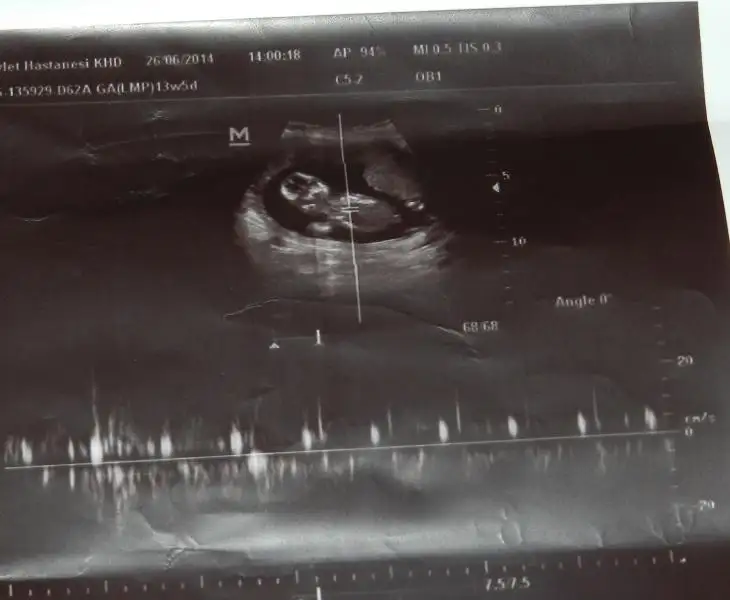

Benim 4 boyutlu değil ama bakabilirmisiniz nubuna. Şu an 13+0 Daha 10 gün var kontrole. Ilkinde 11 hafta 5 gün,ikincisinde 12 hafta 3 günlüktük.

$ImageUploadedByKadınlar Kulübü1403871674.160859.webp